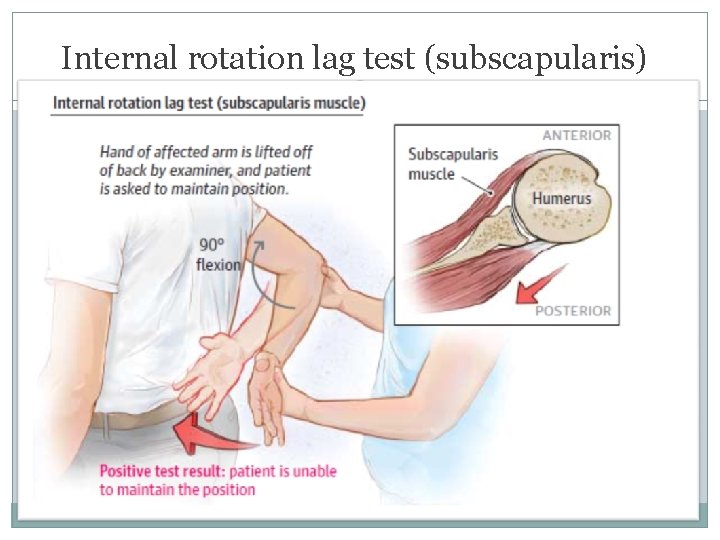

Internal rotation lag test (subscapularis)